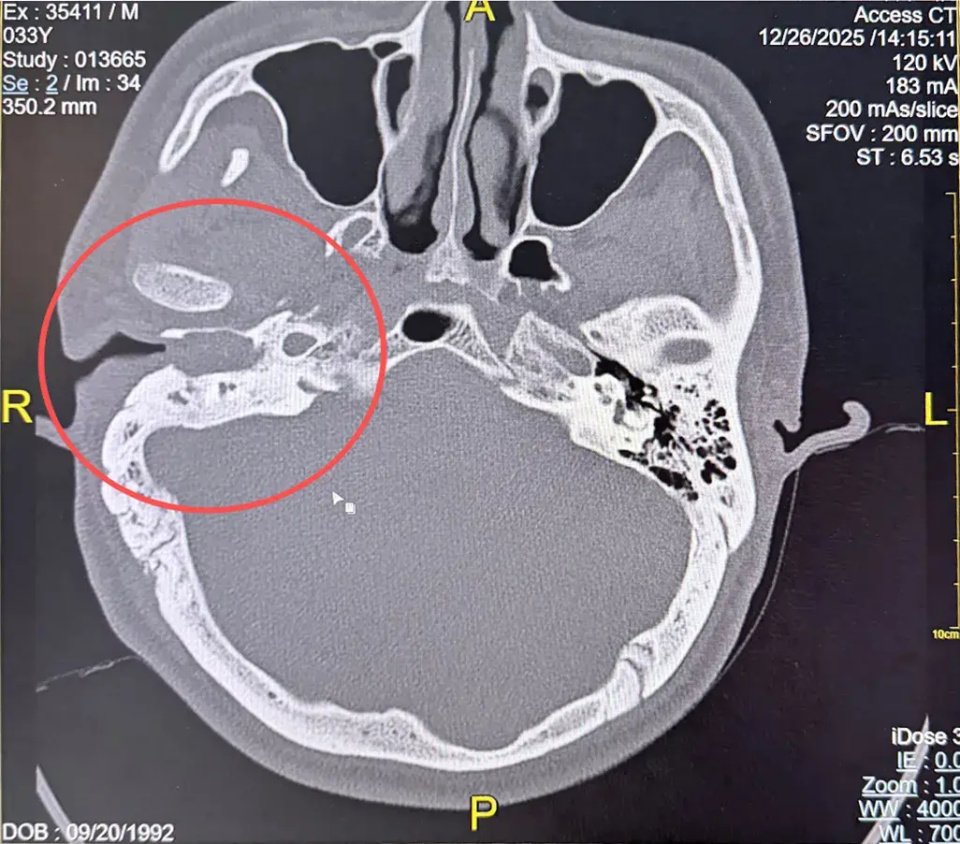

他的右侧耳部,同时盘踞着慢性化脓性中耳炎胆脂瘤型、先天性鳃裂囊肿、先天性耳前瘘管、外耳道胆脂瘤、外耳道异物五种病变。一个耳朵,这么多种严重问题叠加,杨先生自己都难以置信。

这其中,最危险的当属胆脂瘤。它并非真性肿瘤,却有着比肿瘤更可怕的“侵蚀性”——如同蛀虫般不断破坏周围骨骼,一旦侵犯颅底,极易引发脑膜炎、脑脓肿,甚至直接危及生命。

而更棘手的是先天性鳃裂囊肿。人类胚胎发育第4周,头颈部的鳃弓如同精密的“施工蓝图”,分化出面颈部复杂结构,鳃裂本应发育为外耳道,当“施工密码”出错,上皮细胞异常滞留,便会形成贯穿耳、腮、颈的异常管道或囊肿。

杨先生的鳃裂囊肿已深达4公分,且突破了常规病变范围,侵犯至颞下窝——这个被医学界称为“解剖雷区”的区域,成为了手术最大的拦路虎。

颞下窝,是人体头颈部解剖结构最复杂的区域之一。这里不仅密布着神经分支,更有颈内动脉、面神经等“生命红线”穿行其中。

雪上加霜的是,多重病变并非独立存在,而是相互交织形成了复杂的病理网络:胆脂瘤持续侵蚀乳突骨质,有向颅底蔓延的趋势;鳃裂囊肿深扎颞下窝,与面神经分支紧密缠绕;耳前瘘管与外耳道胆脂瘤相互影响,进一步加重耳部感染。这场手术,不仅是对病灶的切除,更是一场在“雷区”中精准游走的极限挑战。